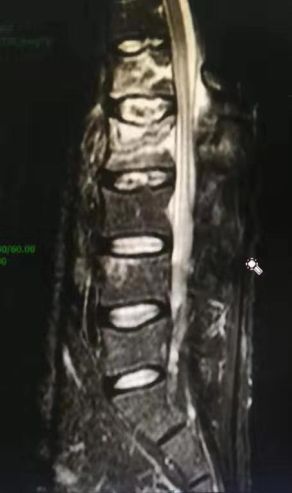

腰椎MRI及CT显示腰1 腰2椎体新鲜压缩骨折